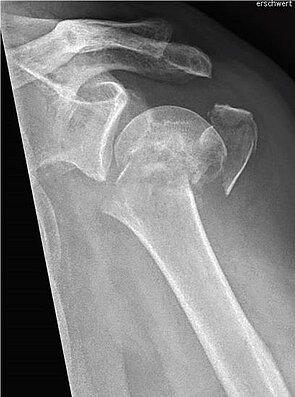

Einen weiteren Schwerpunkt in der Traumabehandlung stellt die Versorgung von Schulterbrüchen dar.

Während bei jüngeren Patienten die Rekonstruktion von Knochen und Gelenken im Vordergrund steht, führt bei älteren Patienten häufig der Gelenkersatz zur schnelleren Wiederherstellung der Beweglichkeit.

Hierfür kann die umfangreiche Erfahrung der orthopädischen Klinik in der Schulterendoprothetik angewandt werden. Dazu werden die Art der Endoprothese und die Einsatzmöglichkeit individuell geplant und umgesetzt.